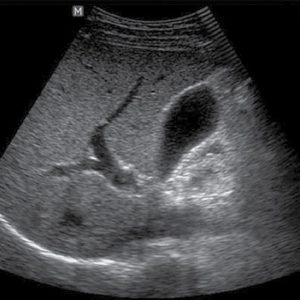

Если у больного возникла желчнокаменная болезнь, то в полости органа проявляются образования. При этом наблюдается утолщенность стенок органа и нечеткое очертание.

При разрастании полипов на стенках желчного пузыря можно заменить образования округлой формы. Если полип имеет размер меньше одного сантиметра и при этом он не растет, то он имеет доброкачественный характер и не повлияет на общее состояние больного. Если образование имеет размер больше одного сантиметра, при этом наблюдается его рост, то это злокачественная опухоль, которая ведет к деформированию желчного пузыря.

Полип в желчном пузыре

| Желчнокаменная болезнь | Истончение стенки около конкремента, тёмное пятно – при отсутствии воспаления можно определить приблизительный состав конкремента по цвету. |

| Полипоз | Определение доброкачественности при динамики изменения размера и формы полипа – 1-2 повторных исследования с 3-недельным интервалом. |